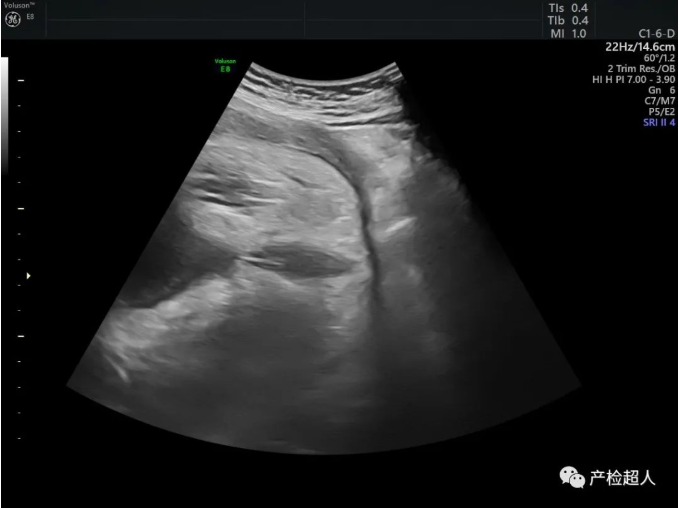

擅长:熟练掌握腹部、成人心脏、血管、浅表器官、关节、妇科、胃肠造影的超声检查,尤其擅长产科以及儿科检查,近15年主要从事产科胎儿畸形的研究,对产前诊断、胎儿宫内发育不同阶段畸形的检测、产后康复及妇产科常见病、疑难病的超声诊断技术娴熟。